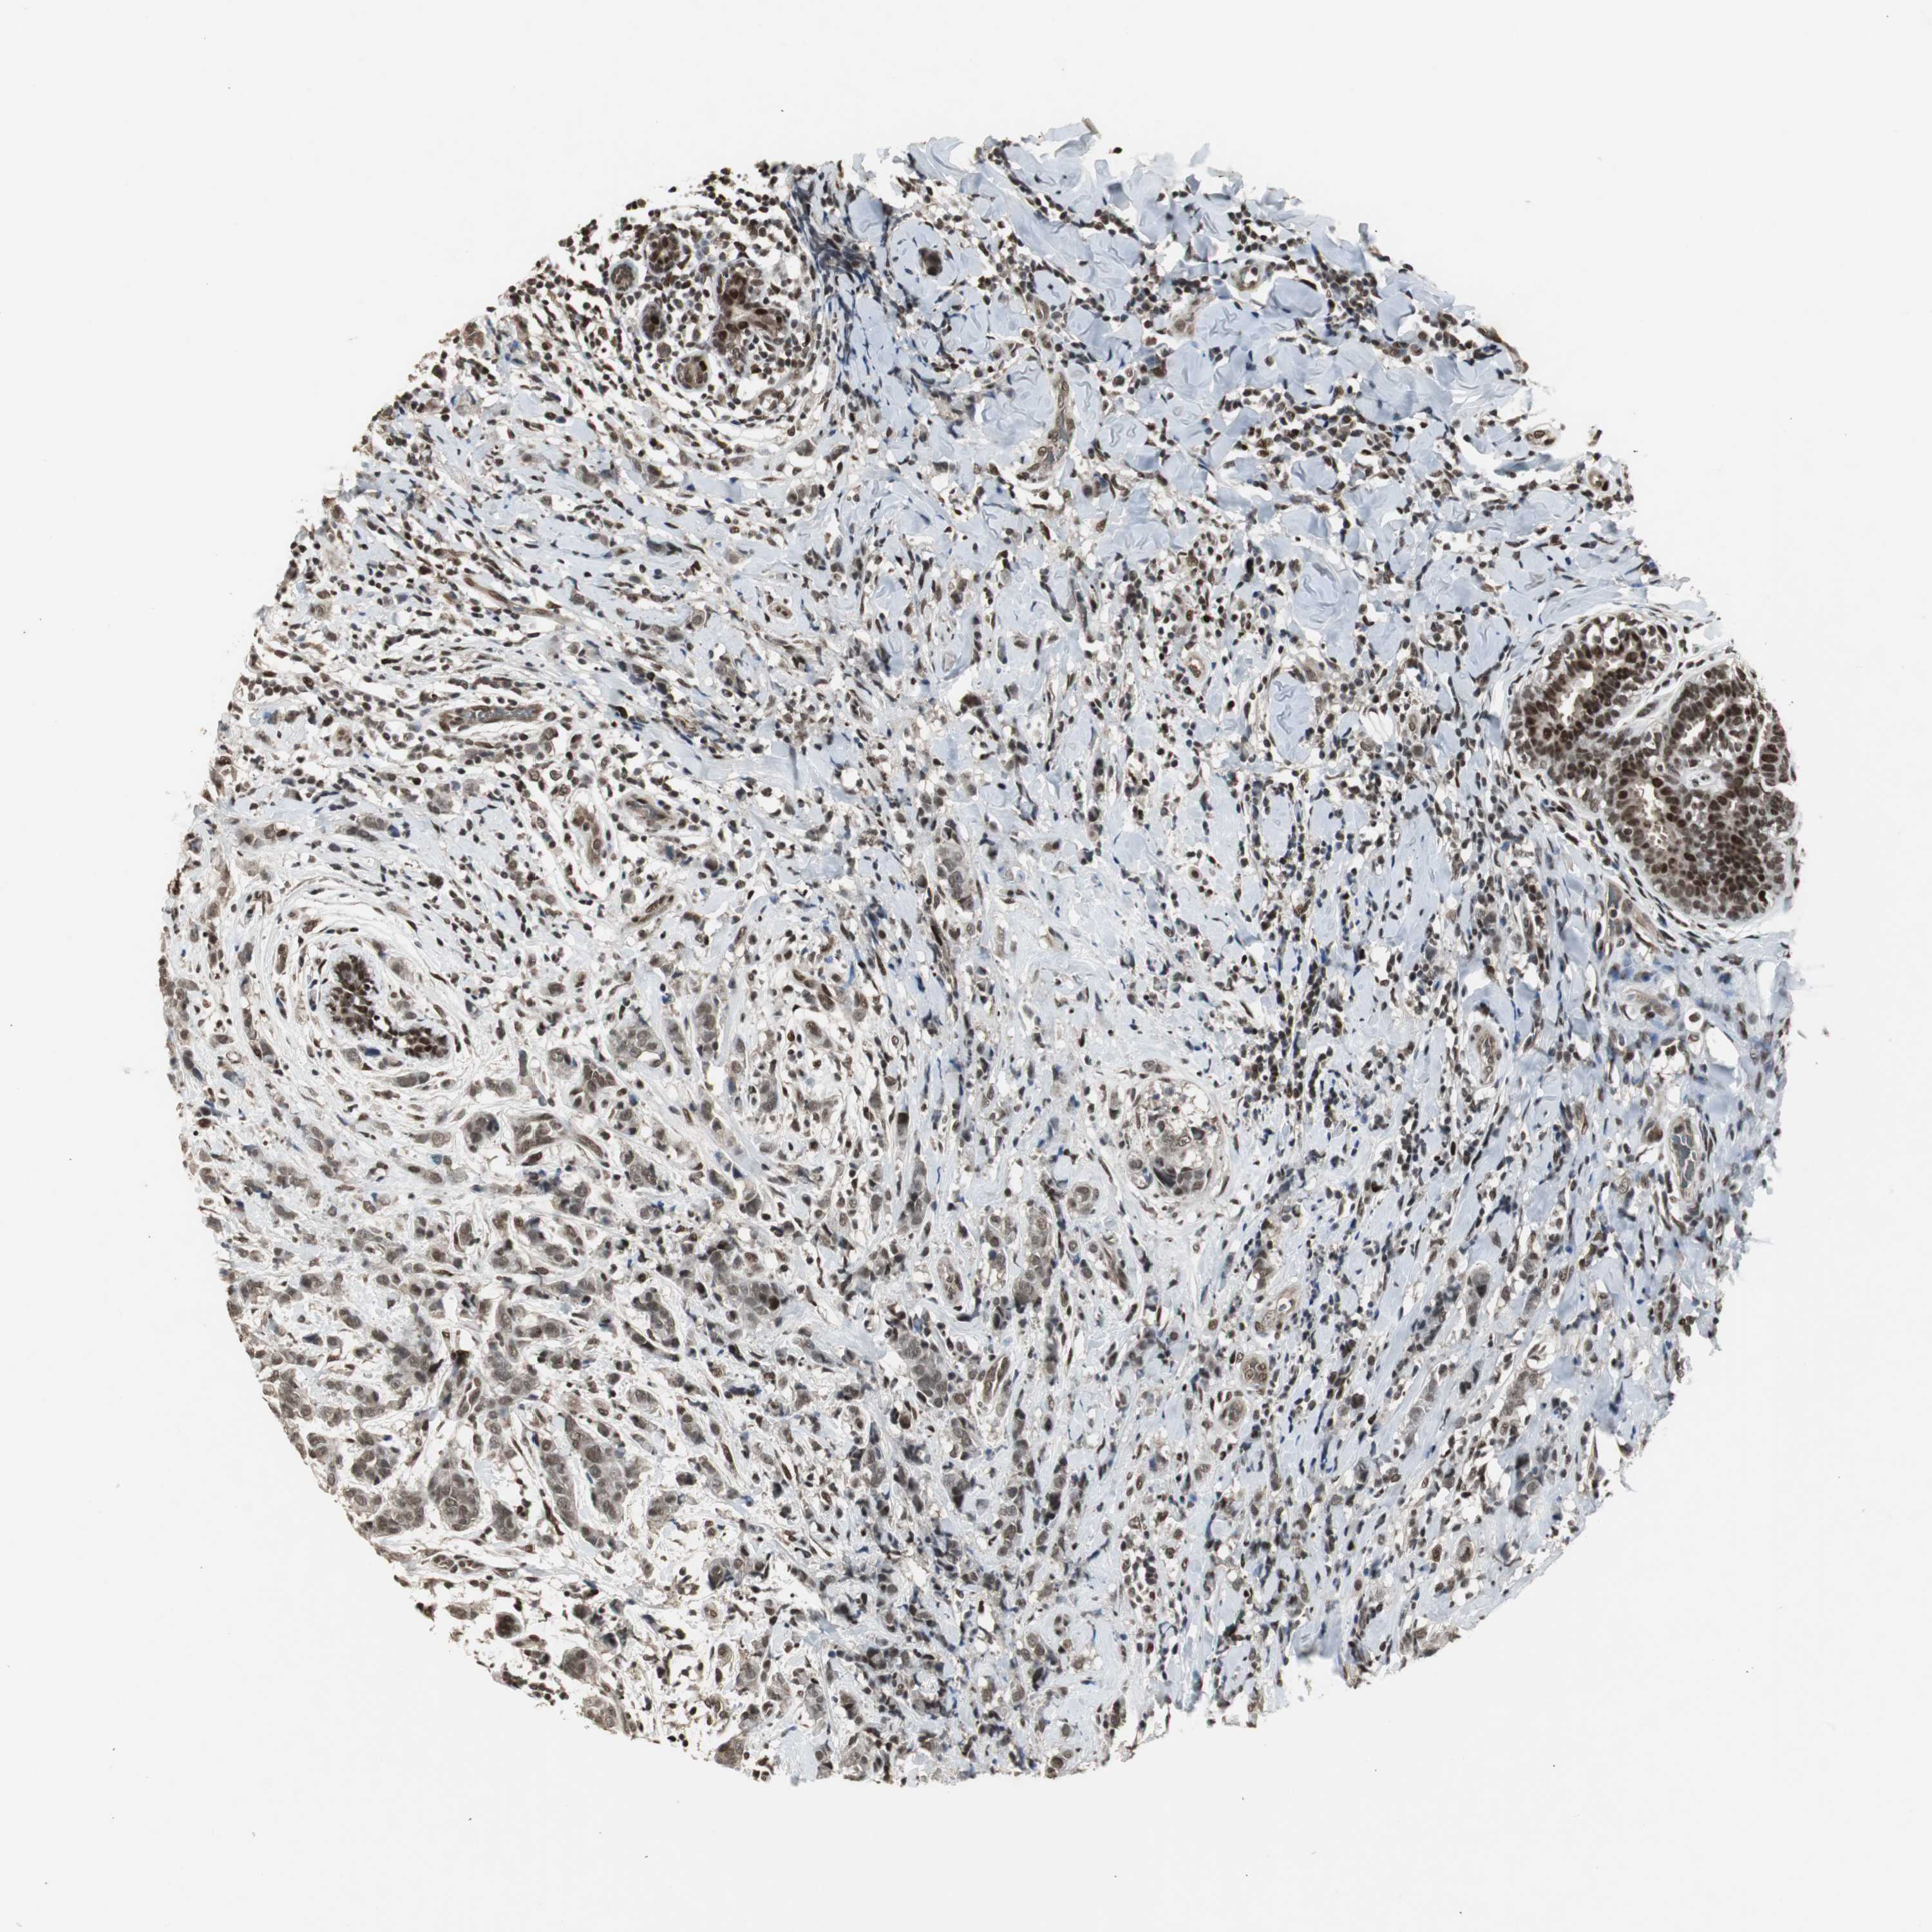

BRCA TCGA BRCA VALIDATION PROTEIN EXPRESSION

ANTIBODIES

AND

VALIDATION